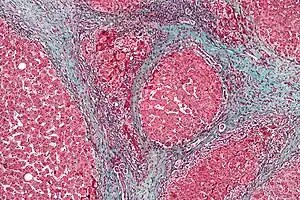

| HRS患者肝硬化的三色染色病理切片的显微照片,肝硬化是HRS常見的病因 | |

研究认为,肝衰竭會改变肠道的血液循环、肾血流量和肾的血管紧张度。因此,肝肾综合征患者的肾衰竭主要是導因於血流动力学的变化,而非肾组织的直接破坏。肝肾综合征患者的肾脏无论在巨觀上或微觀下的病理型態都是正常的,甚至若将之置于健康的环境中(如把他们移植给一个有着正常肝脏的患者),它們仍可正常发挥功能。临床上,肝肾综合征的诊断需對疑似肝肾综合征的患者進行实验室生化指标检查。肝肾综合征可分為兩種類型:1型以快速的肾功能减退为主要表现;2型则表现为腹水的产生,且無法以常规剂量的利尿剂控制。